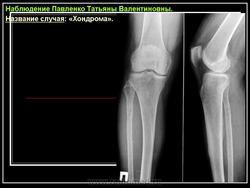

Рентгенологическая картина хондромы представляет четко очерченный опухолевый узел. Очаги минерализации в хондромах выглядят достаточно характерно и представлены очаговыми, глыбчатыми или кольцевидными , арочными отложениями извести. Полного разрушения кортикального слоя трубчатой кости с выходом опухолевых масс в мягкие ткани не наблюдается.